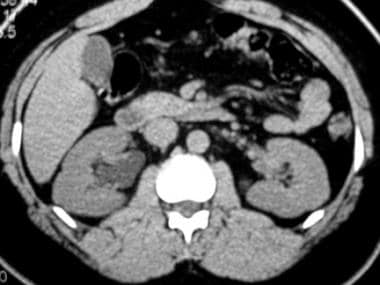

КТ часто використовується для виявлення захворювань нирок, таких як камені в нирках, кісти та пухлини. Зображення, отримані за допомогою КТ, можуть виявити розмір, розташування та форму будь-яких аномальних утворень у нирках. Ця інформація може допомогти лікарям визначити відповідне лікування, наприклад, хірургічне втручання або променеву терапію.